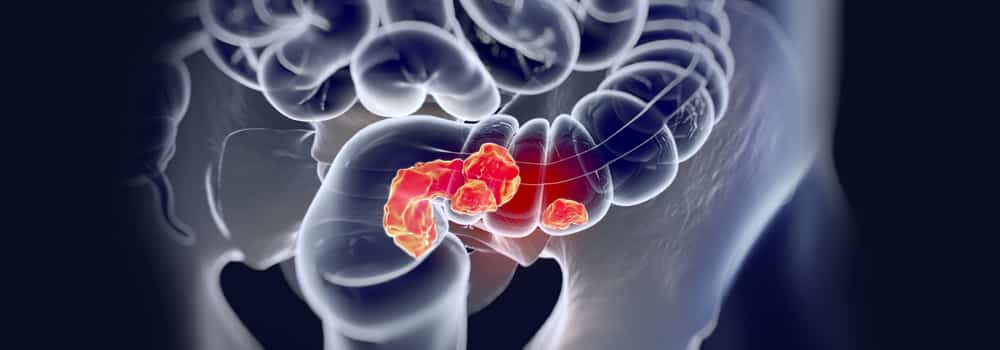

ما أسباب الإصابة بـ سرطان القولون وكيفية الوقاية منه؟

يعد سرطان القولون أحد أكثر أنواع السرطان شيوعًا، وعلى سبيل المثال، يُصاب 1 من 23 رجلًا و 1 من 25 امرأة بسرطان القولون في مرحلة ما خلال حياتهم، ولكن هناك أشياء يمكنك القيام بها للمساعدة في تقليل المخاطر.

أولًا: أسباب الإصابة بسرطان القولون:

1- يتكون سرطان القولون والمستقيم عندما تحدث طفرة في الخلايا تجعلها تنمو وتنقسم دون تحكم، في كثير من الحالات، تموت هذه الخلايا الطافرة أو يهاجمها الجهاز المناعي، لكن البعض منها قد يهرب من جهاز المناعة وينمو خارج نطاق السيطرة ويشكل ورمًا في القولون أو المستقيم.

2- أحد عوامل الخطر هو وجود تاريخ عائلي للإصابة بسرطان القولون أو الأورام الحميدة ما قبل السرطانية، وخاصة عند الوالدين أو الإخوة والأخوات أو الأطفال.

3- كما يؤثر التاريخ الشخصي للإصابة على فرص الإصابة بسرطان القولون، فعلى سبيل المثال، إذا عانى شخص من سلائل القولون السرطانية فمن المرجح أن يصاب بسرطان القولون.

4- يمكن أن تؤدي الإصابة بالتهاب القولون التقرحي أو داء كرون أو داء السكري من النوع 2، إلى زيادة خطر الإصابة بسرطان القولون.

ثانيًا: كيفية الوقاية من سرطان القولون:

1- النظام الغذائي الصحي:

تم ربط الأنظمة الغذائية التي تحتوي على الكثير من الخضار والفواكه بانخفاض خطر الإصابة بسرطان القولون، كما أن تناول القليل من اللحوم الحمراء واللحوم المصنعة يقلل من خطر الإصابة.

2- ممارسة التمارين الرياضي:

إذا لم تكن نشطًا بدنيًا، فقد تكون لديك فرصة أكبر للإصابة به، وقد يساعد زيادة نشاطك في تقليل المخاطر، وتُعد زيادة الوزن أو السمنة سببًا لزيادة فرص الإصابة بسرطان القولون.

3- لا تدخن:

المدخنون على المدى الطويل هم أكثر عرضة من غير المدخنين للإصابة بسرطان القولون.

4- داوم على الفحوصات:

الفحوصات هي اختبارات تبحث عن علامات وجود السرطان قبل ظهور الأعراض، وغالبًا ما تكشف عن نمو في القولون أو المستقيم يسمى الزوائد اللحمية التي يمكن إزالتها قبل أن تتحول إلى سرطان.

ويمكن أن تكتشف هذه الاختبارات أيضًا سرطان القولون في وقت مبكر حينها يمكن علاجه بالدواء، وتوصي جمعية السرطان الأمريكية بإجراء الاختبارات باستمرار بعد سن الـ 45.

وأخيرًا، تُظهر الأبحاث أن العادات الصحية المتعلقة بالنظام الغذائي ومراقبة الوزن والتمارين الرياضية تقلل من خطر الإصابة بسرطان القولون وأنواع أخرى من السرطانات، بالإضافة إلى تقليل فرص الإصابة بأمراض خطيرة مختلفة مثل أمراض القلب والسكري.